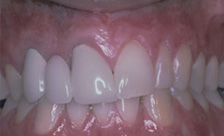

Before and After Pictures of Three Cases of Recession Treated with Soft Tissue Grafting

Case #1

| BEFORE | AFTER |